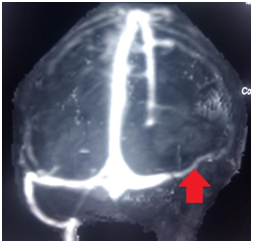

MR venogram showed loss of normal contrast enhancement and flow void involving distal half of right transverse, sigmoid sinus suggestive of thrombosis (Figure 3).

Figure 3 MR venography showing obstruction in the right transverse sinus.